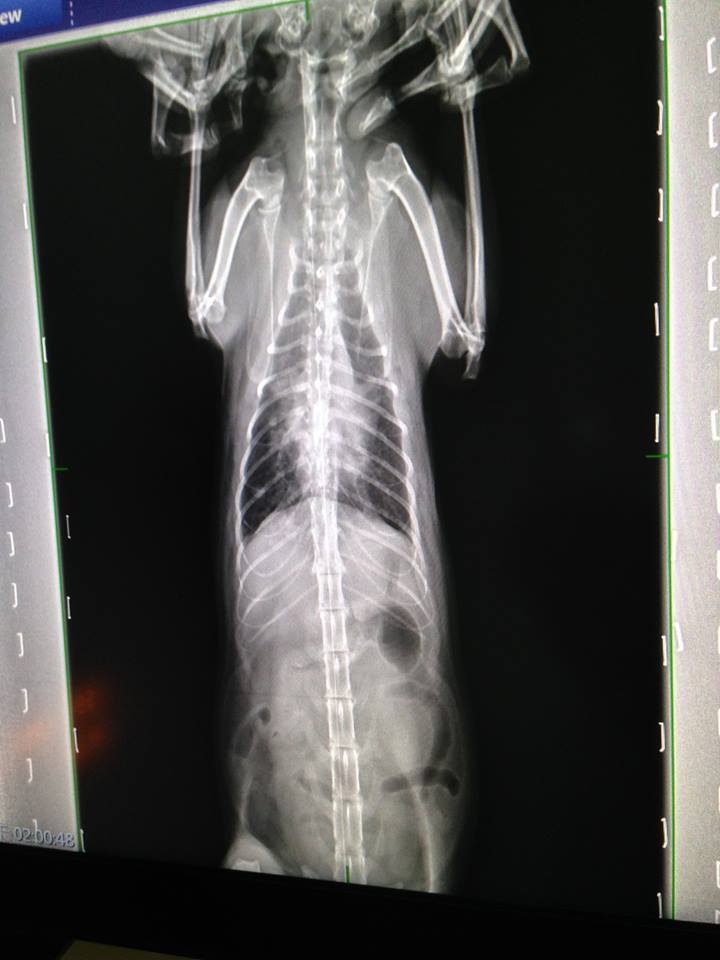

今日有拍X光查看肺部的團塊

肺部與上次相比有較為清澈

拍x光確認肺部的團塊已不如以往明顯

今日同樣有拍X光查看肺部的團塊

左肺跟之前相比乾淨非常多

但在右肺約第8.9根肋骨處從治療前就有個白色結點

現在仍是很明顯,但不確定是否已纖維化